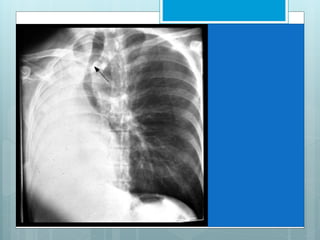

LUL Collapse

Luftsichel, an indirect sign of LUL collapse.

 Its Crescent of aerated lower lobe.

 This represent an incomplete major fissure pulled

forward by atelectatic upper lobe, interposed between

atelectasis & aortic arch.

 Left lower lobe basilar segmental arteries are elevated

and clearly visible in retrocardiac location.